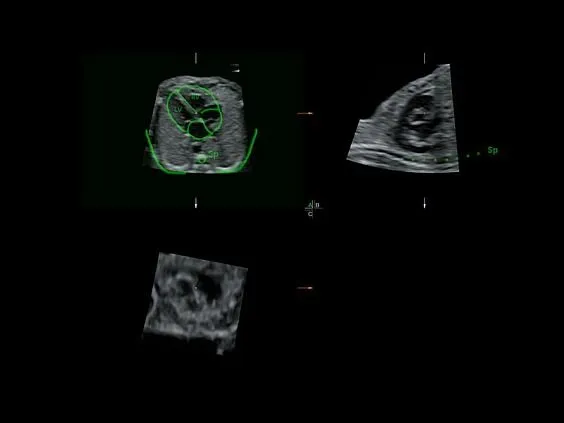

Клинические изображения

- Программа 3D и режим инверсии (при наличии специализированных датчиков).

- Автоматическое определение плода в режиме 3D (SonoRenderLive) — позволяет значительно экономить время и получать изображение конечностей и лица плода в режимах 3D без артефактов и помех — система автоматически определяет границы конечностей и лица плода и выстраивает объемное изображение.

- Программа 3D и режим инверсии (при наличии специализированных датчиков).

- Режим 4D — трехмерное сканирование в реальном масштабе времени.

- Томографический ультразвук (TUI).

- Объемное контрастирование прямой плоскости — Basic VCI (VCI-A + VCI Static).

- Advanced VCI (Volume Contrast Imaging) — расширенный программный пакет объемного контрастного изображения (VCI) для объемных датчиков:

- Проведение любой произвольной плоскости в 3D/4D (OmniView).

- Объемное контрастирование любой произвольной плоскости (OmniView+VCI).

- Регулировка толщины и формы коронарного среза в 3D/4D (получение коронарной плоскости в 3D/4D, например, для оценки мозолистого тела — автоматическая функция «Corpus Callosum»).

Главное достоинство Voluson E8 — качество изображения. Система обеспечивает превосходную чёткость и контрастность как в двухмерном, так и в трёхмерном и четырёхмерном форматах. Она оснащена современными допплеровскими режимами для анализа кровотока и передовыми инструментами трёхмерной реконструкции. Встроенные интеллектуальные алгоритмы автоматизируют многие процессы, что позволяет врачу работать быстрее и точнее.

УЗИ аппарат Voluson E8 оснащён фирменным пакетом технологий HDlive, который формирует реалистичные изображения благодаря использованию многоточечных источников света и объёмного моделирования.

Кроме того, аппарат поддерживает Advanced VCI (Volume Contrast Imaging) для оптимизации толщины срезов и повышения контрастности в объёмных исследованиях, а также технологию OmniView, которая позволяет получать изображения в нестандартных плоскостях при анализе сложных объектов.